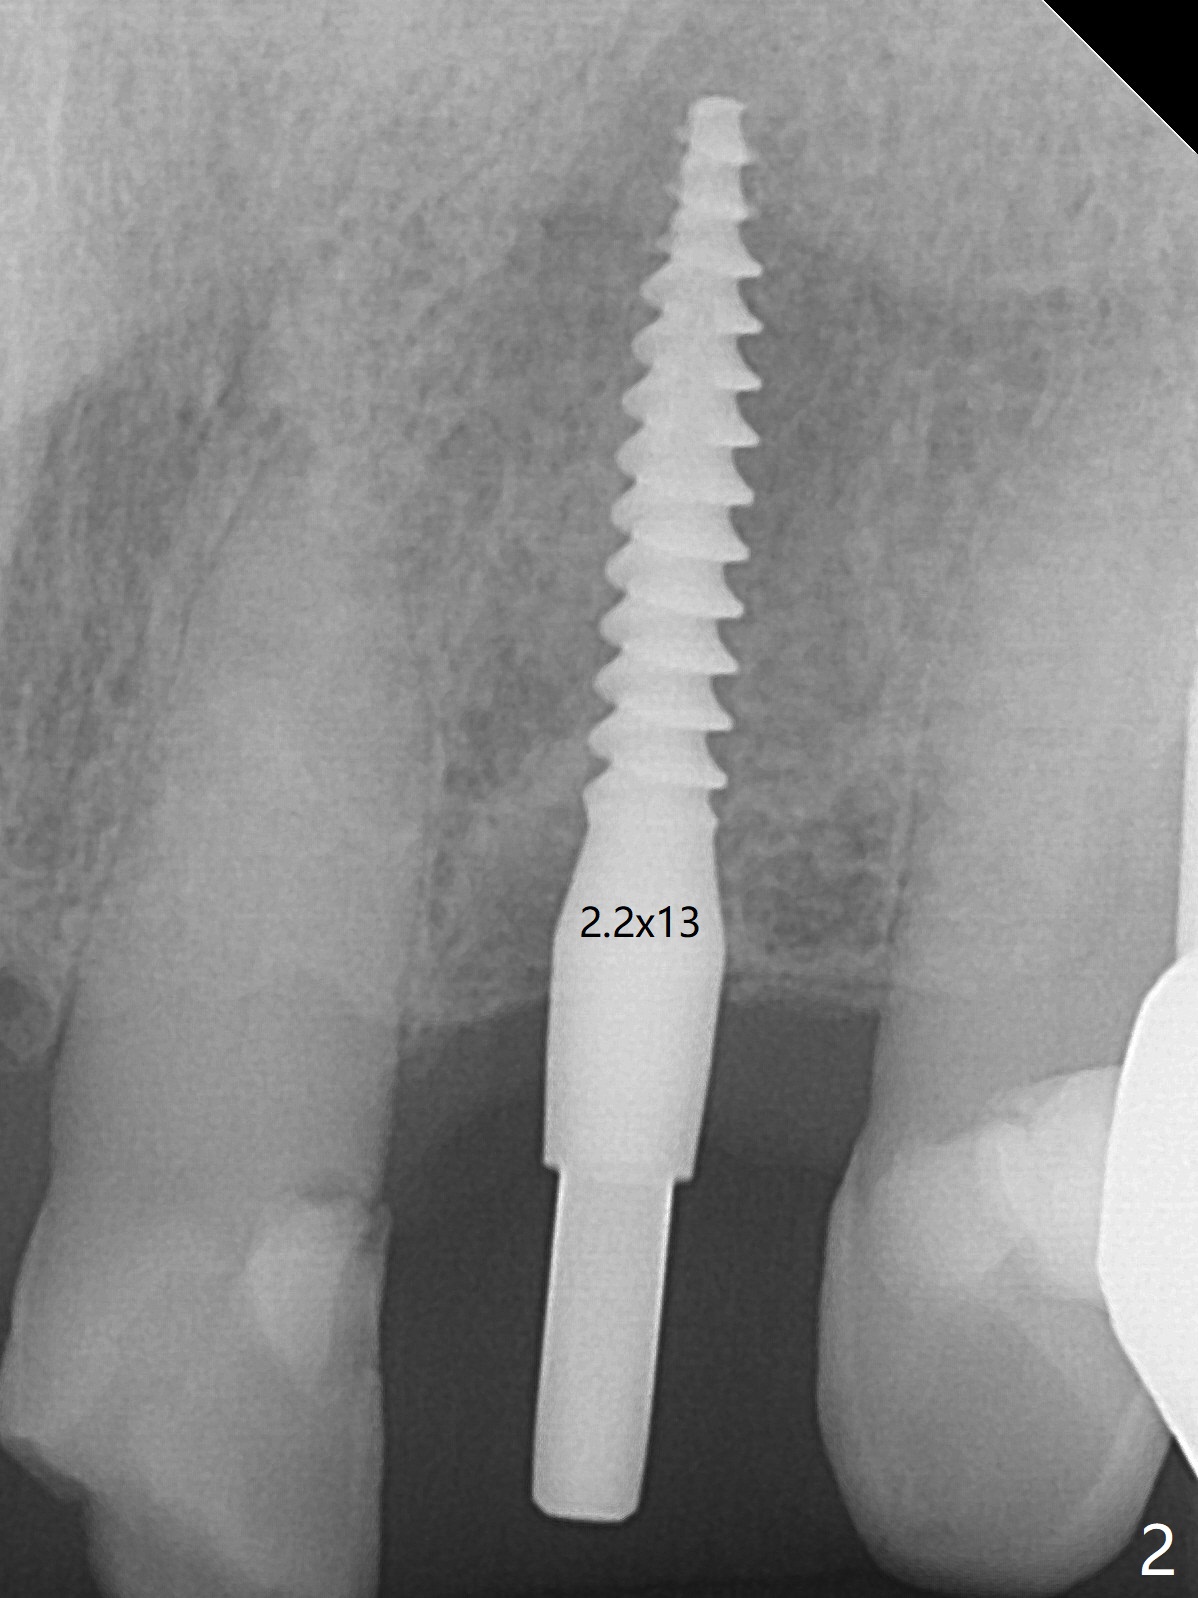

After undersized drilling in depth at #10 (2.2x13 mm (10.5 mm offset), Fig.1), a 2.5x13 mm 1-piece implant is placed (Fig.2,3), as compared to the design (Fig.3'). Following 3 more turns of the implant (~ 20 Ncm), bone graft and heavy buccal reduction of the coronal end of the abutment, an immediate provisional is bonded to the tooth #9 (Fig.4) and splinted to the tooth #11 with a twisted wire (Fig.5). To increase stability and reduce reduction, a 3 mm 1-piece implant could be used with 15 degree abutment. The implant remains stable 5 months postop (Fig.6). The implant seems to be flexible before heavy occlusal reduction; note the periimplant micro-space (Fig.7). The patient is a bruxer. The implant crown seems to be minimally mobile 2 months post cementation (Fig.8, without treatment). 牙冠粘固后1年1个月软硬组织正常(图九)。